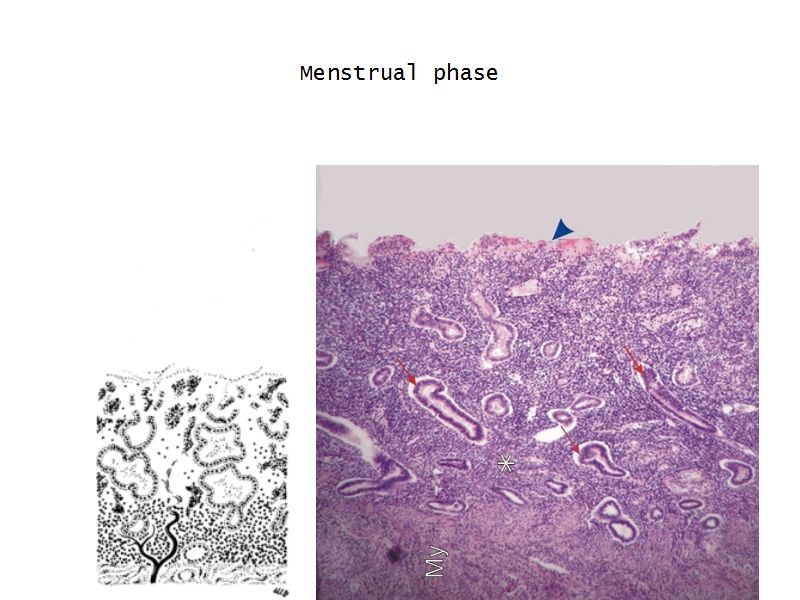

Menstrual phase

- Vasoconstriction

- Ischaemia

- Necrosis functional layer

- Basal layer

- No necrosis

- Short straight vessels